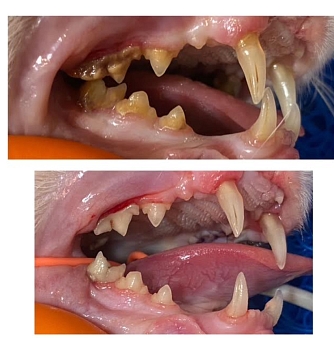

Die grösste Baustelle aber war und ist ihr Gebiss:

Bisher wurde eine Seite behandelt, einige Zähne sind dabei praktisch fast von alleine raus gefallen andere mussten gezogen werden.

Da ihr aufgrund ihres Alters keine zu lange Narkose zugemutet werden sollte, wurde erst eine Seite ihres Gebisses gemacht, die andere Seite folgt in einigen Wochen.

Bereits jetzt speichelt sie weniger und macht allgemein einen besseren Eindruck. Karisma hat vermutlich viele Jahre unter schlimmen Zahnschmerzen gelitten.

Karisma lebte über 16 Jahre auf der Strasse und war nie bei einem Tierarzt. Das hat Spuren hinterlassen. Vor allem an ihrem Gebiss. Jetzt wurde sie umfassend untersucht und ihr Gebiss saniert